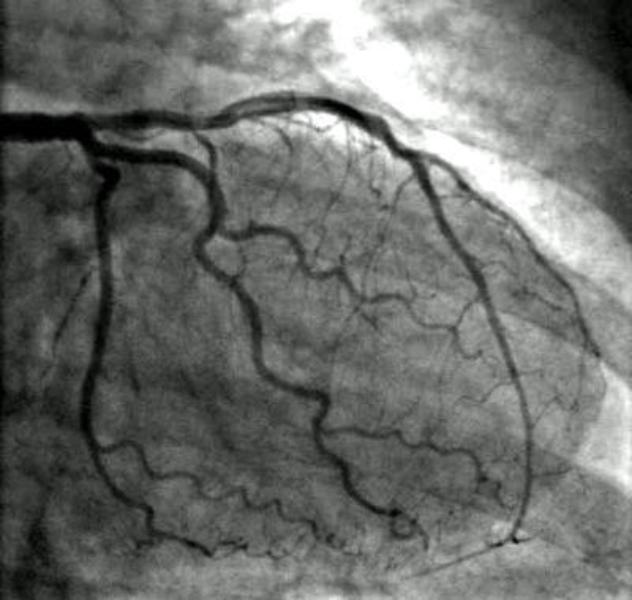

Image Gallery

Pictures That Speak